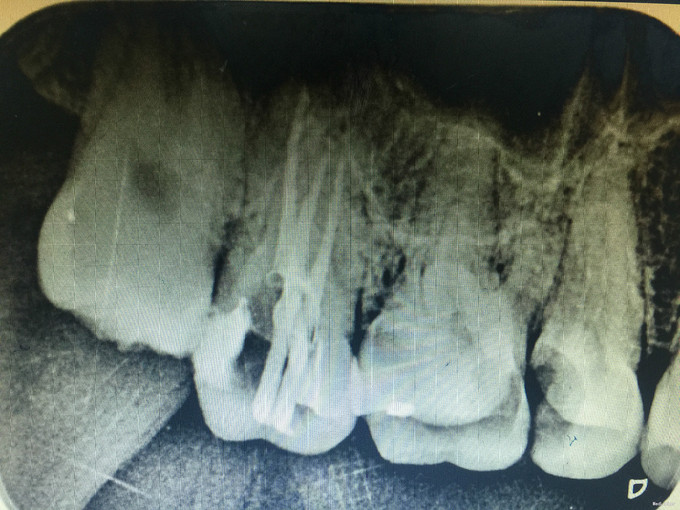

临床检查:17远中及牙合面充填物未脱落,探(+-),冷(+-),叩(-),松动度(-),牙周正常. 辅助检查:X线示17龋坏近髓腔。

诊断:17继发龋 治疗:经患者知情同意后,17局麻去除原有充填物降牙合,开髓拔髓寻找根管口,建立直线通路,扩通根管,确定工作长度。S3/EDTA凝胶镍钛器械,低浓度次氯酸钠冲洗根管,预备至35/04,氢氧化钙诊间封药,一周后复诊,试主尖X线示恰充,试干根管,导AH-PLUS糊剂,VDW热压胶垂直加压根充,术后见根管恰充,暂封调合抛光。术后观察嵌体修复。